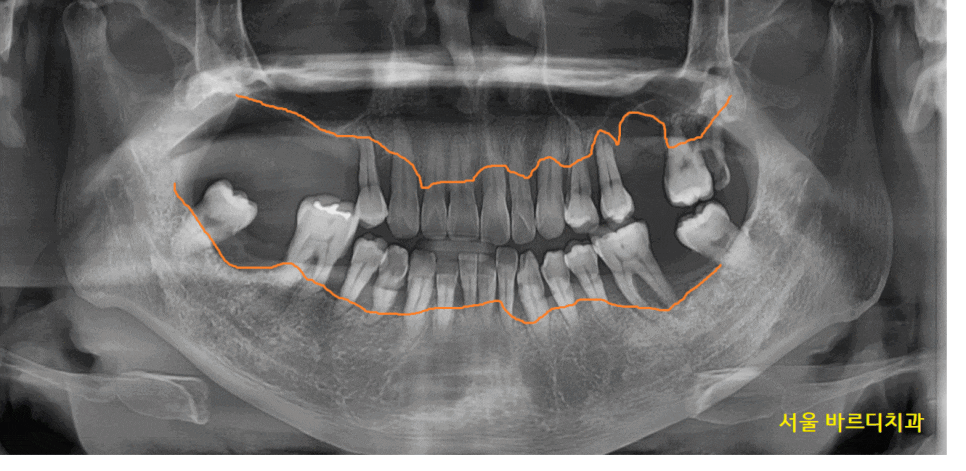

환자분을 처음 뵈었을 때

솔직히 말씀드려 안 흔들리는 치아가 없었습니다.

잇몸이 많이 망가졌어요.

윗니는 개수로만 4개 없음

아랫니는 2개 없음

이건 이미 뽑힌 상태만 세었을 때이고

뽑을 치아도 상당했습니다.

윗니 어금니 부분 예시를 보여드리면..

어금니 대부분이 잇몸뼈가 거의 없어서

뿌리만 잡고 있는 정도였거든요~

상악동까지 거리 3.4mm

임플란트는 최소 8mm정도 심으니까

만들어야할 양만해도 5mm가 넘네요.